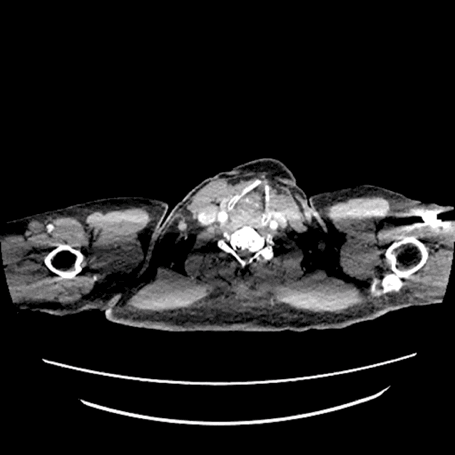

术前CTA详解:

主动脉弓部动脉瘤,紧贴左锁骨下动脉开口,主动脉弓部大量附壁血栓。左颈总后缘处主动脉直径35mm,左锁骨下动脉前缘主动脉直径37mm,左锁骨下动脉后缘主动脉直径38mm,颈动脉后缘到瘤体中心线长度18mm,左颈总动脉距离左锁骨下动脉9mm。锁骨下动脉粗大,根部直径14mm*17mm。

术前三维重建/CTA